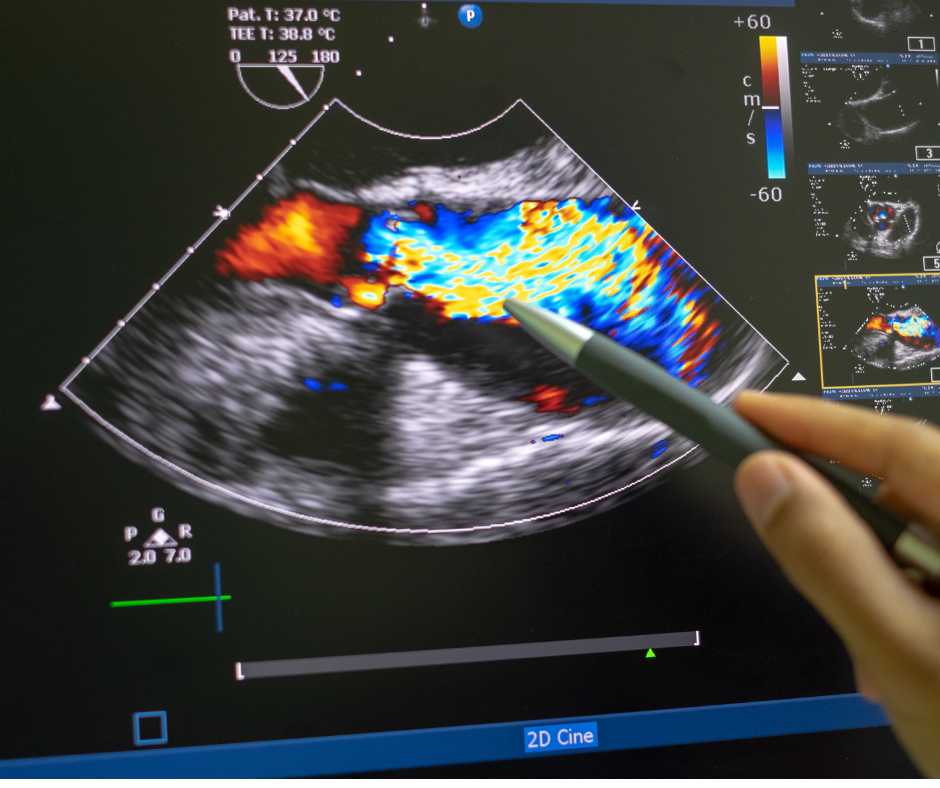

4. Ultrasound

Your obstetrician may perform an ultrasound to confirm:

- your due date

- check the baby’s growth and developent

- detect any potential early issues